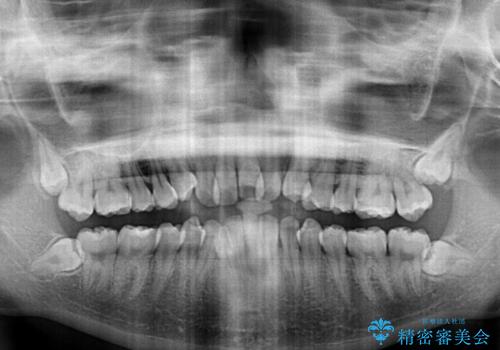

- 前歯のデコボコやクロスバイトと上顎の前突感による口の閉じにくさを気にして来院された患者様です。

目立たない装置を希望されたので、上顎が裏側装置のハーフリンガルを選択し、上下左右の小臼歯(計4歯)を抜歯して矯正治療を行うこととしました。